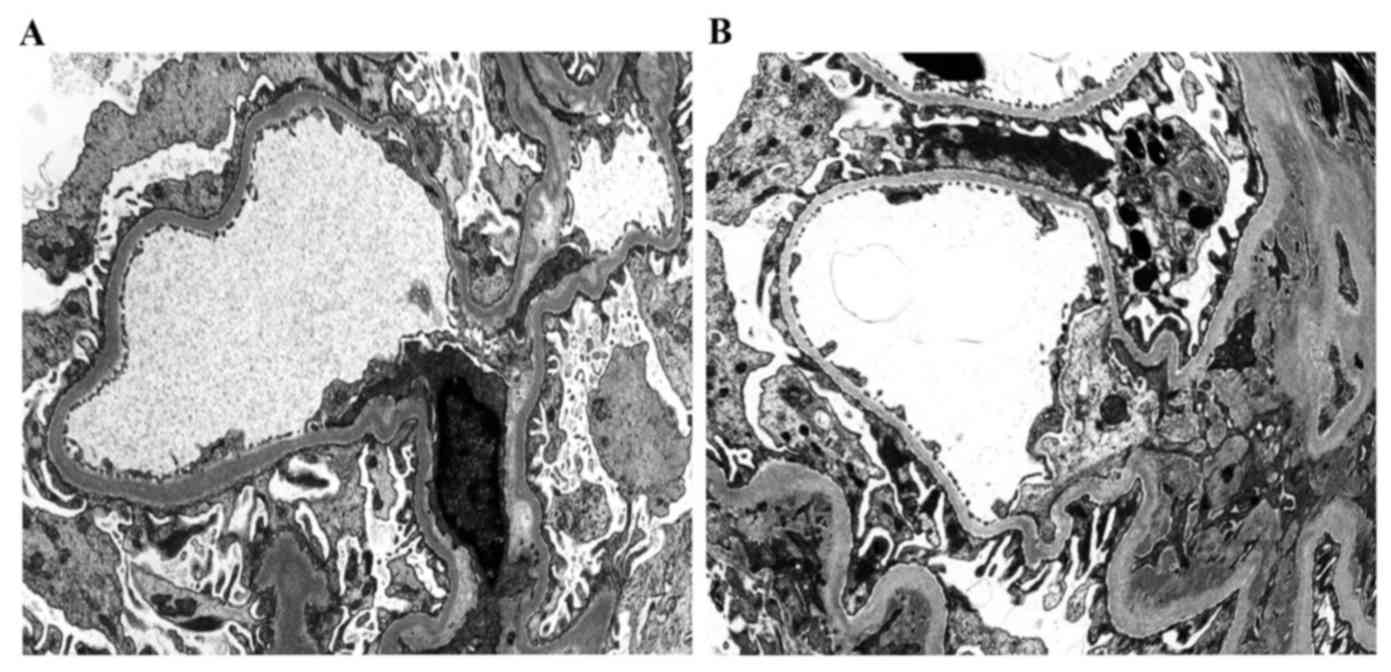

HMGB1, TGF‑β and NF‑κB are associated with chronic allograft nephropathy

The present study aimed to investigate the association between high mobility group protein B1 (HMGB1), transforming growth factor‑β1 (TGF‑β1), nuclear factor‑κB (NF‑κB) and chronic allograft nephropathy (CAN) and to identify the clinical significance of HMGB1, TGF‑β1, NF‑κB on patients with CAN. Between September 2012 and November 2014, 27 patients with CAN diagnosed by biopsy were enrolled in the present study and a further 30 patients that underwent nephrectomy following trauma were selected as the control group. Immunohistochemical staining with HMGB1, TGF‑β1 and NF‑κB expression in the renal tissues, and western blot analysis were used to measure the relative expression of HMGB1, TGF‑β1 and NF‑κB. Reverse transcription‑quantitative polymerase chain reaction (RT‑qPCR) was used to estimate the relative expression of HMGB1, TGF‑β1 and NF‑κB mRNA. Statistical analysis was used to calculate the association between HMGB1, TGF‑β1 and NF‑κB expression and CAN grade. Immunohistochemical staining demonstrated that HMGB1, TGF‑β1 and NF‑κB had markedly positive expression rates in renal tubular epithelial cell cytoplasm and membranes in CAN renal tissues, and the positive rates of HMGB1, TGF‑β1 and NF‑κB increased with the aggravation of CAN pathological grade (I, II and III). The results of western blot analysis indicated that the expression levels of HMGB1, TGF‑β1 and NF‑κB were significantly higher in the CAN group, compared with the normal group (P<0.05), and the expression levels increased with the progression of CAN grade. A positive association among HMGB1, TGF‑β1 and NF‑κB expression was identified. RT‑qPCR analysis demonstrated that the expression of HMGB1, TGF‑β1 and NF‑κB mRNA in the CAN group was significantly higher than in the normal group (P<0.05), and the relative expression level of HMGB1, TGF‑β1 and NF‑κB mRNA not only increased with the aggravation of CAN grade, but was also positively associated with the expression of HMGB1, TGF‑β1 and NF‑κB, respectively. The abnormal expression of HMGB1, TGF‑β1 and NF‑κB is therefore, an important manifestation of CAN and the expression of HMGB1, TGF‑β1 and NF‑κB mRNA in the renal tissues are significantly associated with CAN pathological progression. HMGB1, TGF‑β1 and NF‑κB may form a signaling pathway that leads to the occurrence of CAN, which induces renal interstitial fibrosis.

Figure 1